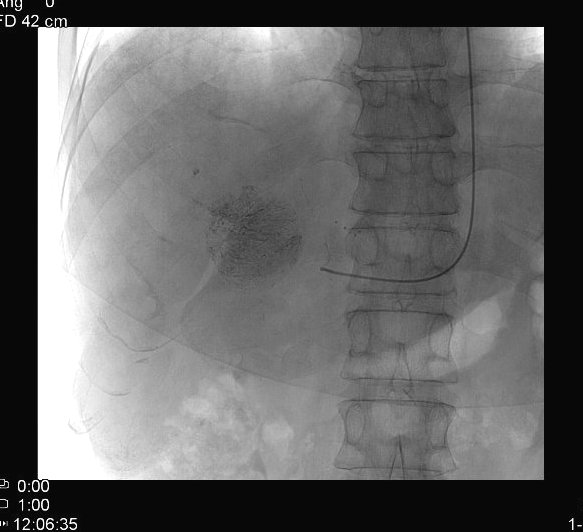

Ethanol causes dehydration and coagulation necrosis of the tumor cells, followed by fibrotic degeneration. After alcohol injection, a typical “snow storm like”, hyperechogenic area can be seen in the treated area (figure 15.).

Image

Figure 15. – PEIT (Percutaneous Ethanol Injection Therapy), confirmed HCC with biopsy